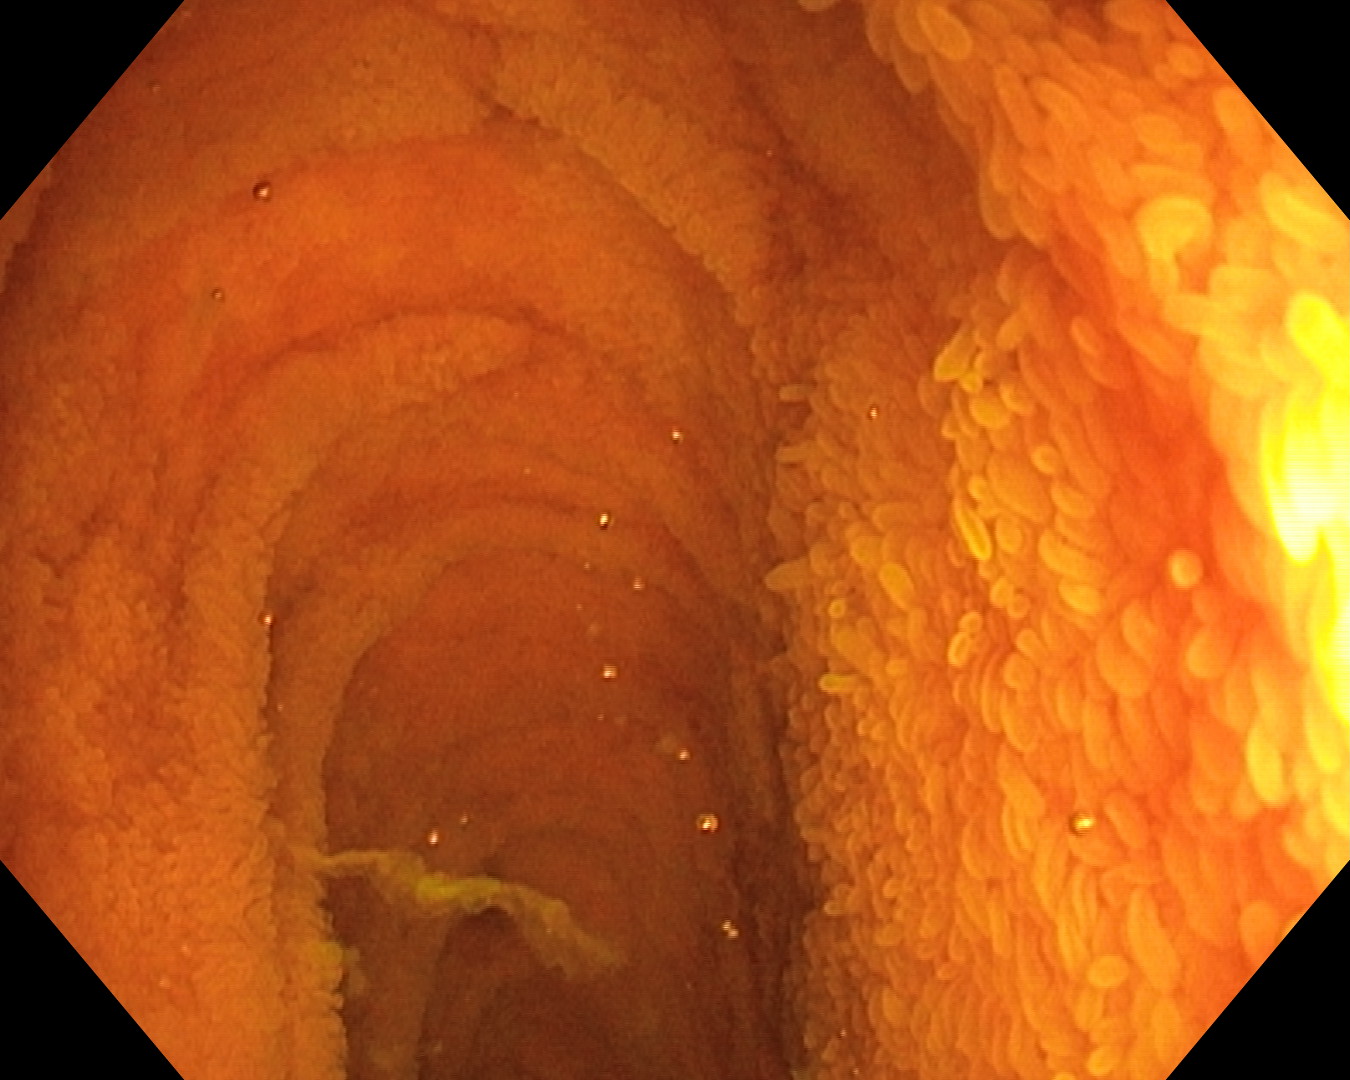

Enteroscopia se folosește doar la pacienții cu rezultate negative la colonoscopie și gastroscopie, dar care prezintă hemoragii „oculte” – care nu pot fi observate cu ochiul liber, dar care apar la analizele de laborator – în materiile fecale. Aceste hemorogii trebuie să aibă o proveniență nespecificată, existând suspiciunea unor sângerări la nivelul intestinului subțire. De fapt, scopul enteroscopului este tocmai examinarea acestei sângerări inexplicabile.